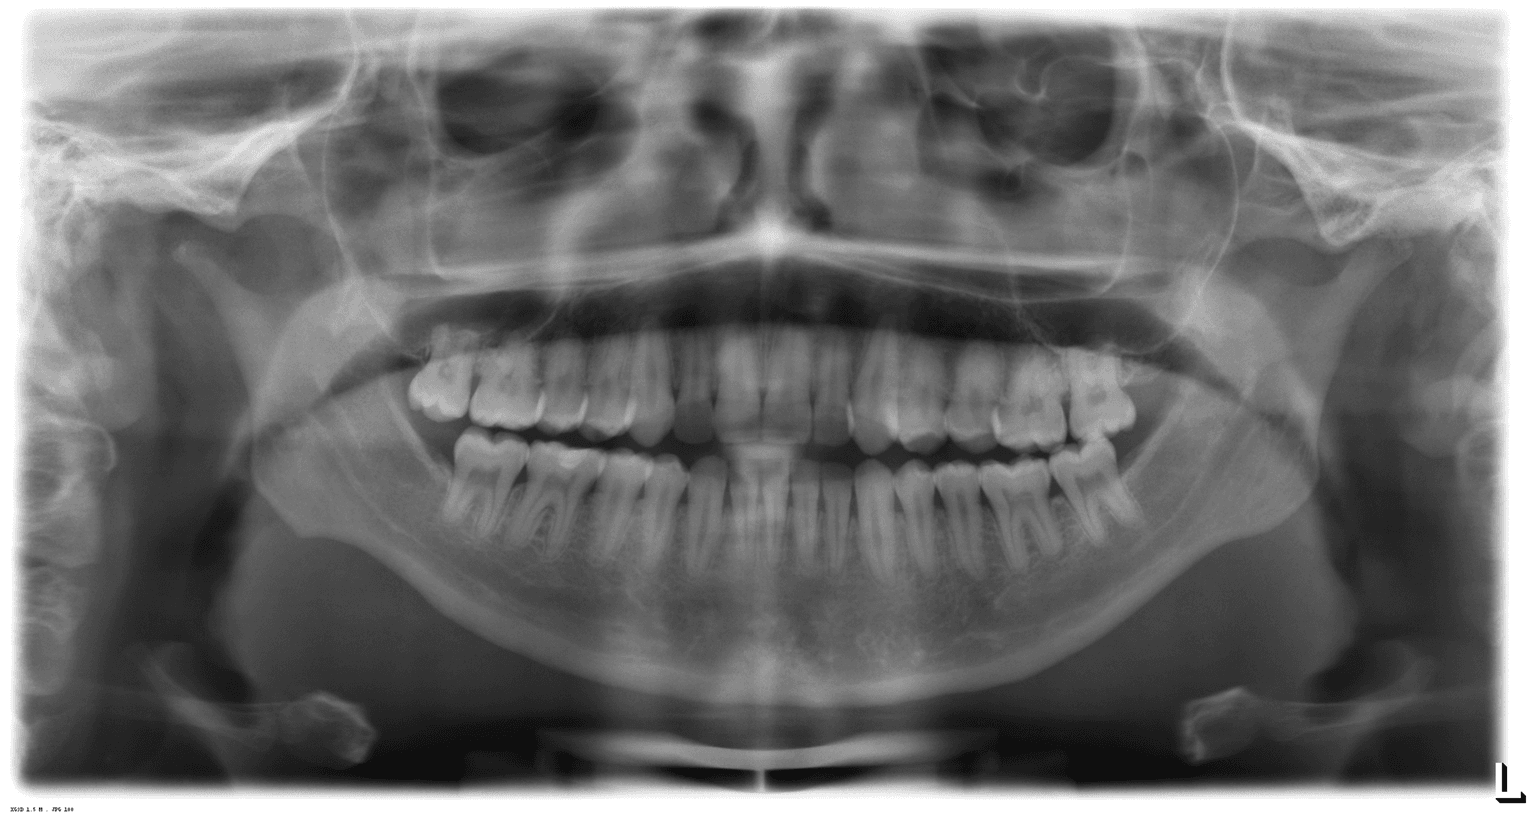

A radiografia panorâmica é indispensável para a avaliação de possíveis lesões endodônticas, inclusive em dentes que já tenham tratamento de canal realizados. Visto que a movimentação ortodôntica pode agudizar processos infecciosos que estejam “adormecidos”.